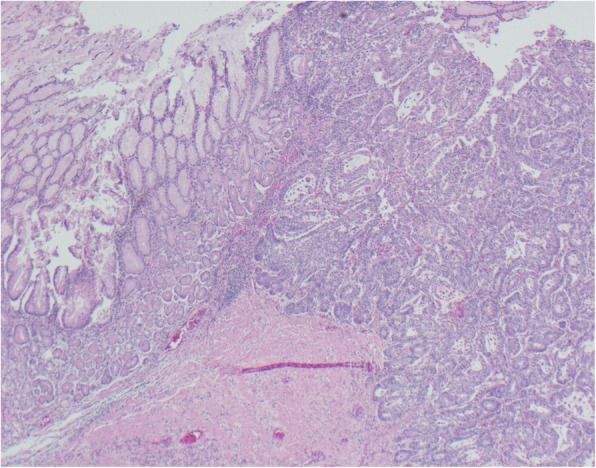

Для обеспечения эвакуации из желудка временно установлен покрытый стент размером 23 × 100 мм. По данным патомофологического исследования биоптата подтверждена аденокарцинома (рис. 4).

Рисунок 4 [2].